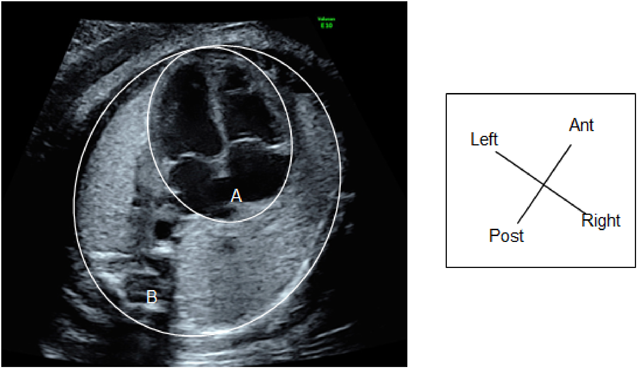

i. Total cardiac dimension

The so-called ‘total cardiac dimension’ (TCD) is a distance between the outer attachments of the mitral and the tricuspid valves near the epicardial AV junction (Fig. 5a). At 22 or more weeks of gestation, the normal TCD value (in millimeters) is approximately equal to the figure of gestational weeks. Prior to 22 weeks of gestation, the TCD value needs to be compared to references. Otherwise, the cardio-thoracic area ratio (CTAR) should be measured to assess the cardiac size in a proportional sense. When the estimated weight of the fetus does not correspond to the figure of gestational weeks, the TCD cannot be used as an evaluation marker of the cardiac size (Fig. 5b).